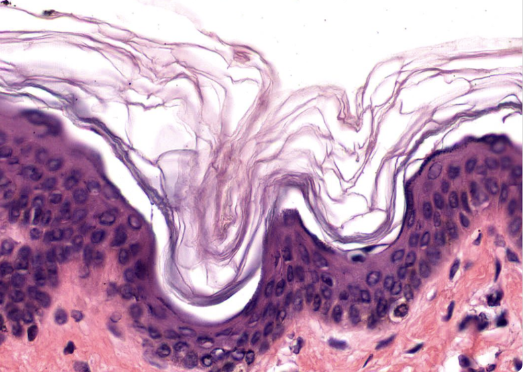

Epithelial Tissues Matching Game

Test your knowledge about epithelial tissues with this fun matching pairs game!